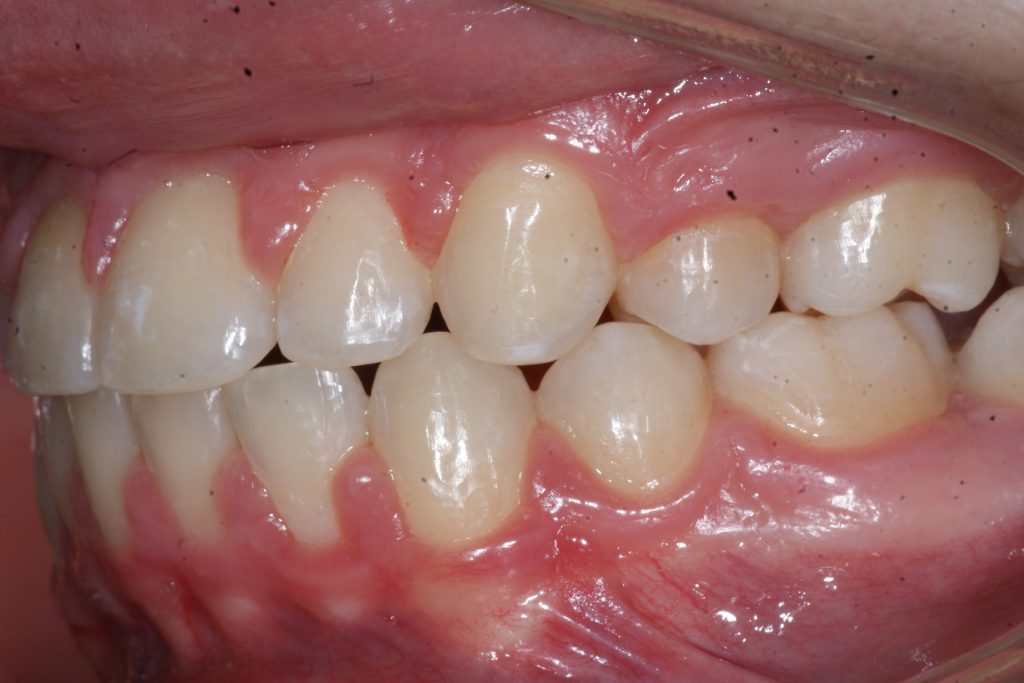

Correction d’une malocclusion de type Classe II avec chevauchement sévère aux 2 arcades. Des appareils fixes (boîtiers), une expansion palatine et l’extraction de 4 prémolaires (#14-24-35-45) furent nécessaires pour améliorer ce sourire. Traitement chez un adolescent, réalisé en 28 mois.